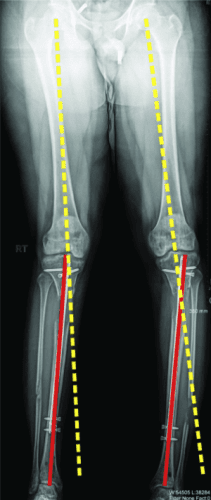

轴向偏斜是胫骨中更常见的问题。胫骨往往会延长成外翻和外翘。为防止这种情况,钉子应插入正确的起点,该起点非常高,并且尽可能靠后,在胫骨的外侧,并在额平面的膝盖中心。如果指甲与截骨术上方的外侧皮层之间有空间,则应在该空间中插入阻挡螺钉。如果指甲与后皮层之间有空间,则在那里插入另一个阻挡螺钉。我设计了 STRYDE 钉子,通过提供第三个近端锁定螺钉(P2.2 只有两个)来抵抗轴向偏差。如果遵循所有这些预防措施,则不会随着延长而出现屈曲或外翻畸形。

敲击(外翻)鞠躬(内翻)

屈曲(procurvatum)

在外部机构胫骨身材延长并出现双侧并发症的患者。他发展了胫骨和 Abu/a 延迟结合,右侧是敲击 {外翻),左侧是弓形 {内翻),两侧是 f1exion {procurvatum}。我们在手术室使用临时外部斧头机对两侧进行了急性矫正,并放置了新的胫骨杆。我们在 Abu/a 延迟结合上放置了逆行杆。